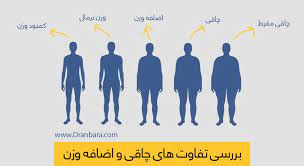

قیمت: 22٬000 تومان - دسته بندی فایل: علوم پزشکیپاورپوینت چاقی و اضافه وزن

فروش ویژه پاورپوینت حرفه ای چاقی و اضافه وزن با تخفیف استثنایی فقط 42000 هزار تومان تعداد اسلاید : 15 اسلاید